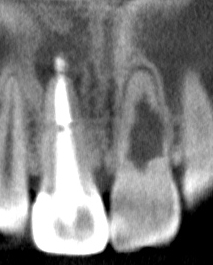

左上顎中切歯:抜歯即時埋入・即時負荷によるインプラント埋入、CTG(結合組織移植術)、セラミッククラウンによる上部構造

前歯部インプラントにおける当院のこだわり

前歯は抜歯をすることで、歯根からの血流供給を受ける束状骨が必ず吸収し、唇側のボリュームが失われます。良好な審美性を維持するため、当院では陥没する歯肉を補うCTG(結合組織移植)を基本的にルーティンで行っています。

治療前後の写真です。ホワイトニングも行い、口腔内全体が明るい印象になりました。 レントゲンでは、右上顎中切歯の透過像は縮小しており、根尖性歯周炎は治癒傾向にあります。

患者様の熱心な口腔衛生環境の維持にも助けられ、スムーズな治療経過を辿ることができました。